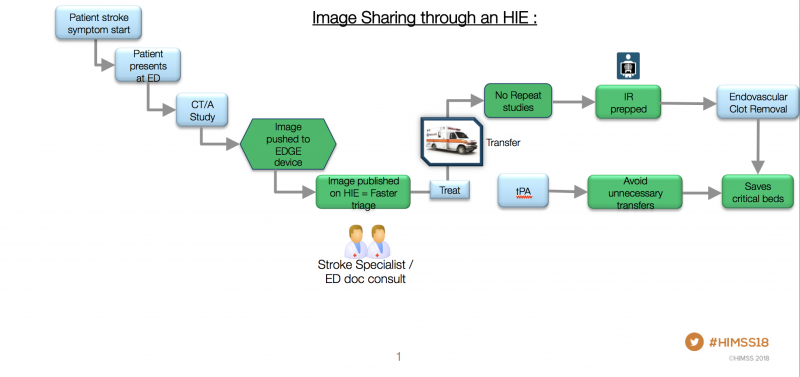

A regional image exchange system is saving lives and reducing radiology costs in Maryland by improving the efficiency ...